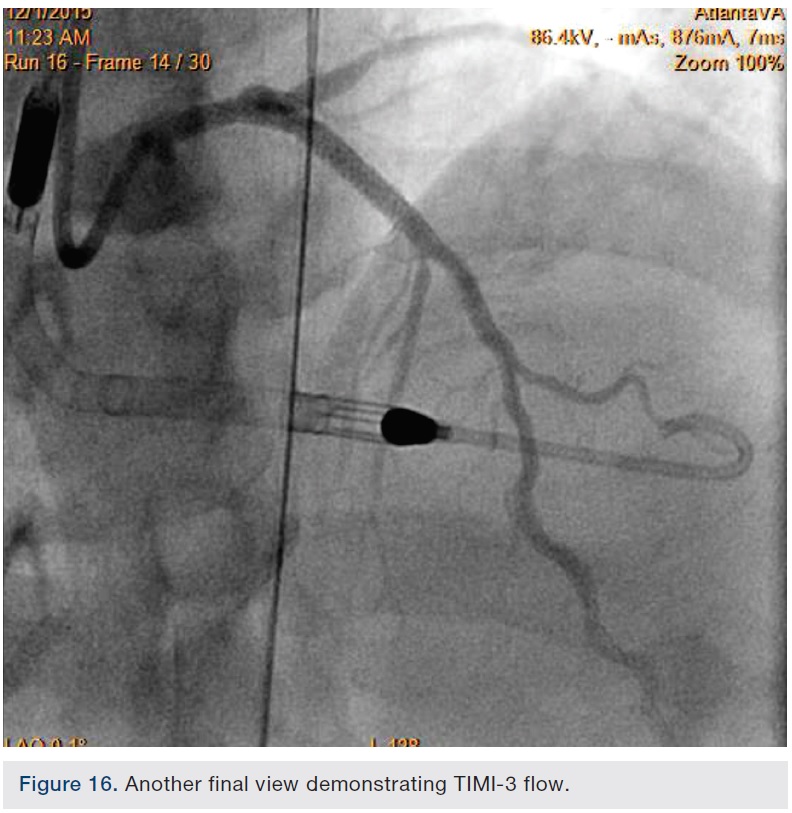

Following successful completion of the peripheral phase, it was felt that a 4-week period was necessary for the iliac stent to heal somewhat (especially since we planned to place a 14 French Cook sheath through it). We then moved on to the coronary phase of this procedure. Bilateral groins and the right wrist were prepared and draped in the usual sterile fashion. Using micropuncture technique with fluoroscopic verification of needle entry into the left CFA at the upper quadrant of the femoral head, a 6 French sheath was placed in the left CFA. The existing left femoral arterial sheath was removed, and the arteriotomy was pre-closed with a single Perclose device (Abbott Vascular). The arteriotomy was then serially dilated with 10, 12 and 14 French dilators, and a 14 French, 30 cm Cook sheath was placed successfully in the left common femoral artery. Following therapeutic anticoagulation with intravenous heparin, a regular J-wire and a 6 French pigtail catheter were used to cross the aortic valve, and the catheter was used to exchange the J wire for the 0.018-inch Platinum Plus wire (Boston Scientific). The Impella CP (3.5) percutaneous left ventricular assist device (LVAD) (Abiomed) was inserted into the left ventricle over the Platinum Plus wire (Figure 8). The Impella was then activated and good flows were verified. Right radial artery access was obtained and a PB 3.0 7.5 French sheathless guide system (Asahi Intecc) was used to engage the left main coronary artery. The LAD was wired uneventfully using a Runthrough wire (Terumo) via a 1.25 x 6 mm over-the-wire (OTW) Sprinter balloon (Medtronic). This was then exchanged for a Viper wire (CSI). Orbital atherectomy of the proximal LAD lesion was performed with excellent results (80,000 rpm x 4 passes, 120,000 rpm x 2 passes) (Figure 9). The LAD wire was then exchanged for a Runthrough wire and the left circumflex (LCX) was wired with a BMW wire. Following plaque modification with orbital atherectomy, predilation of LAD was performed with 3.0 x 20 mm Chocolate Balloon (QT Vascular Ltd) (15 atmospheres x 60 seconds and 15 atmospheres x 30 seconds) (Figure 10) with an excellent result and no dissection (Figure 11). A 3.5 x 38 mm Promus stent (Boston Scientific) (14 atmospheres x 30 seconds) was placed from the left main into the proximal LAD lesion ensuring adequate coverage. The jailed LCX wire was recovered and re-placed in the LCX through the struts of the newly placed LM-LAD stent (Figure 12). Predilation of the LCX ostium was performed with a 2.5 x 8 mm Glider balloon (QT Vascular Ltd) (14 atmospheres x 25 seconds). The mid LAD was stented (ensuring overlap with proximal stent) with 3.0 x 16 mm Promus stent (16 atmospheres x 25 seconds). A final kissing balloon inflation of the LAD/LCX with an NC Sprinter 2.5 x15 mm balloon (Medtronic) into the LCX and a NC Sprinter 3.5 x12 mm balloon into the LAD was performed, with up to 16 atmospheres x 20 seconds on both (Figure 13). Final IVUS of the LM and LAD stent revealed excellent results and the LCX ostium looked excellent as well (Figures 14-16).